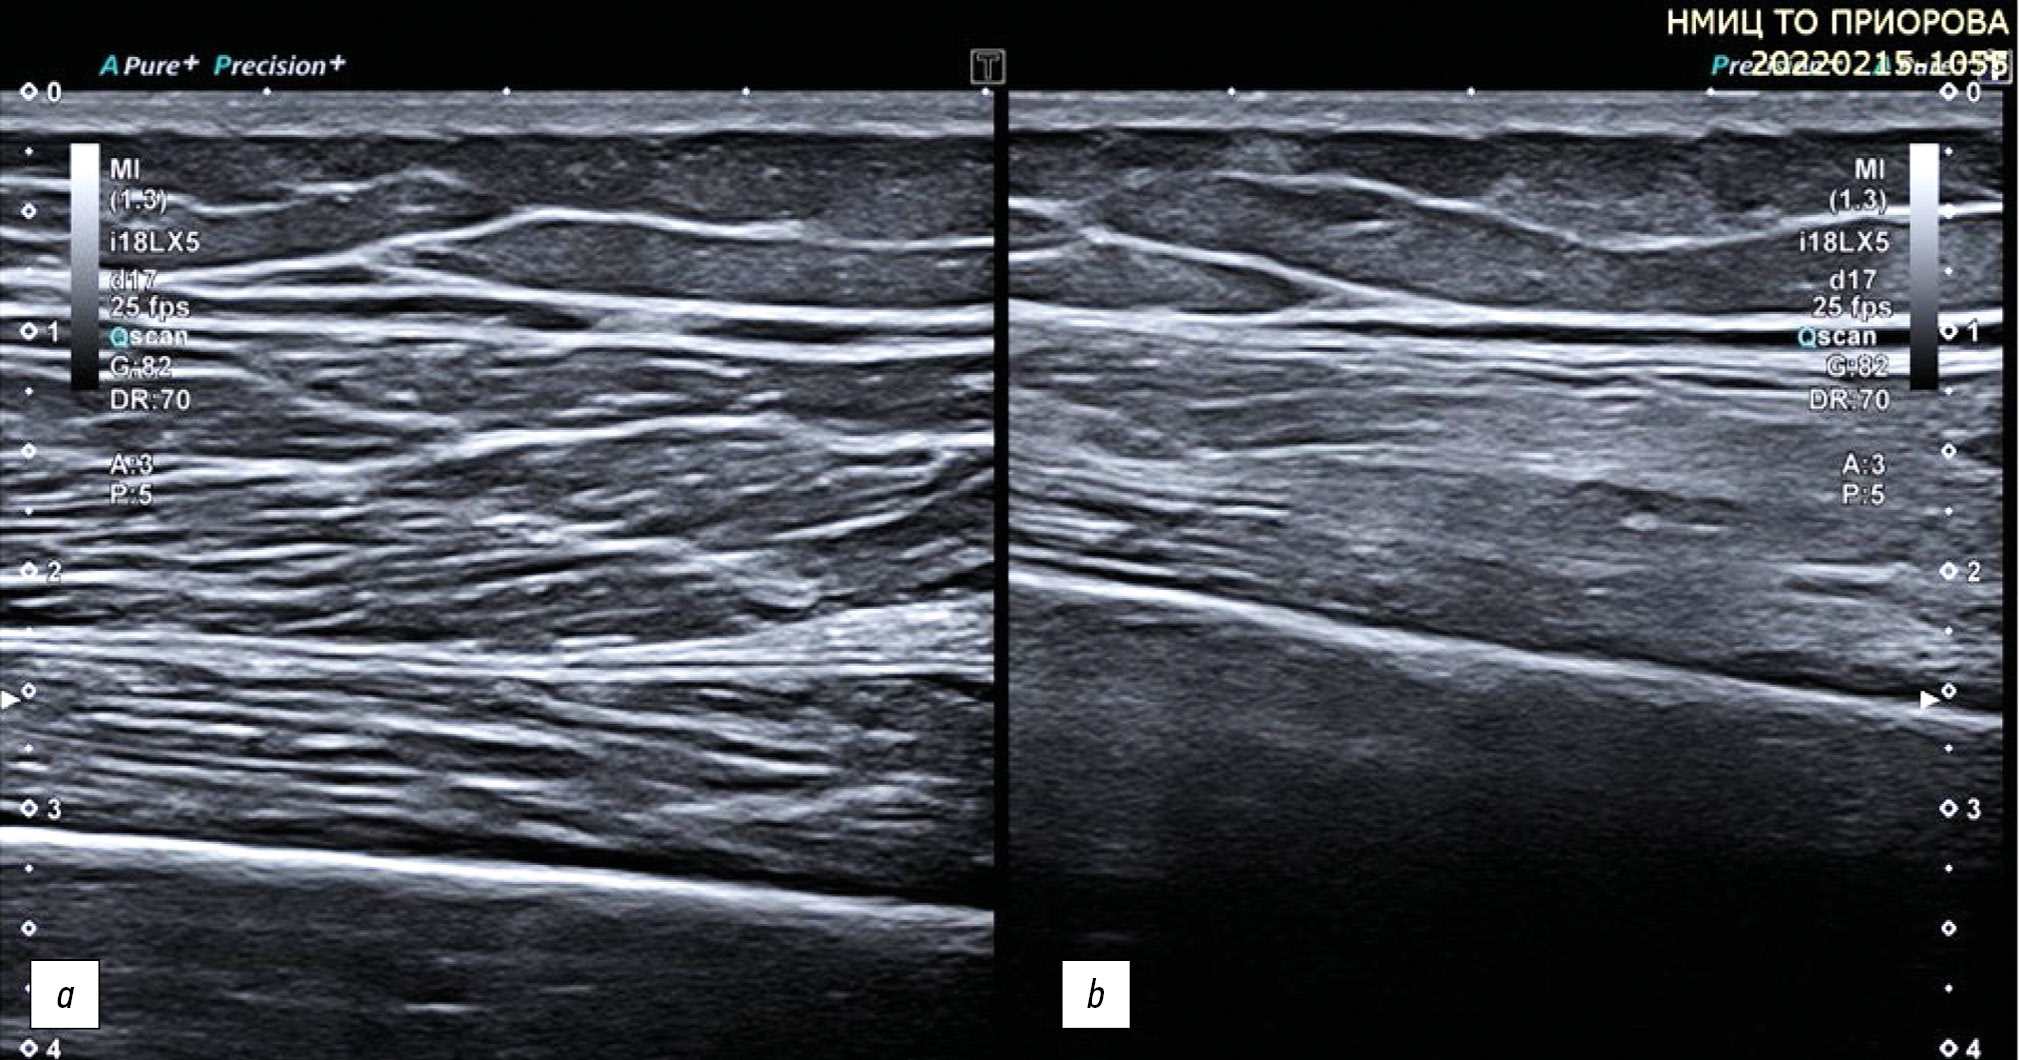

IL-1β, IL-17, and TNF-α can disrupt the normal biological activity of tenocytes and contribute to the onset of tendon disorders, which cause potential exacerbation of degenerative tendon diseases and the related inflammatory processes [2] (Fig. 5).

Fig. 5. Longitudinal sonogram of tenosynovitis of the tendons of the long flexors of the second finger of the foot (a) and the flexor tendons of the third finger of the hand (b). Signs of tenosynovitis on ultrasound are similar in both cases and are characterized by thickening of the tendon, fluid in the synovial membrane, and hypertrophy of the synovial wall of the tendon sheath. Using the color Doppler imaging mode, blood flow in the synovium is observed .